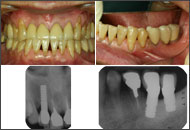

インプラントの場合、審美性を追求すると清掃性に問題が生じ、逆に清掃性を追求すると審美性は劣ってしまうという二律背反の要素の兼ね合いが重要である。そこで必要な清掃性を確保しつつ、その中でできるだけ審美性を追求することになる。1ピースの場合、2ピースほど冠のマージンが歯肉縁下深くないので口腔清掃上は有利であるが、セメント合着するので、歯肉縁下が深すぎると、余剰セメントの完全除去が困難となり、余剰セメントの残留が原因で慢性インプラント周囲炎を起こし、骨吸収を招くことがあるので注意が必要である。そのためには冠装着後のデンタルX線写真でセメント取り残しのチェックと、6ヵ月後健診でもデンタルX線写真とポケット検査を行うことが重要であると思う。もし、骨吸収やポケットデプスが進み、プロービングで疑わしい場合はフラップを開けてセメント掻爬をやるくらいの勇気が必要と思う。インプラントの近遠心での骨変化はデンタルX線写真に反映するが、唇・口蓋側での初期の骨吸収はX線像に現れないので注意が必要である。私は合着に3Mビトレーマ(グラスアイオノマー系レジンセメント)を使用してきたが、昨年発売になった余剰セメントの一塊除去がし易いというセールスポイントの松風ハイボンドレジグラス(同系統)なども試用している。

| 1ピースAQBインプラントの課題 | ||

![]() ? 2000/09/01 左上5、左上6 連結MBCr装着時 |

![]() ? その2Y後にみられた残留セメントの褥瘡による頬側粘膜の穿孔(fenestration) |

![]() ? 2005/05/18 粘膜退縮により残留セメントは消失している |